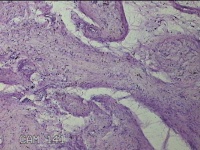

子宫体肌瘤结节

性别

女

年龄

32岁

临床诊断

子宫肌瘤 疤痕子宫

一般病史

发现子宫肌瘤数月余。

标本名称

大体所见

灰白色圆柱形条索状组织10x7.5x1.8㎝一堆,切面均为灰白色结节状或编织状,质中。